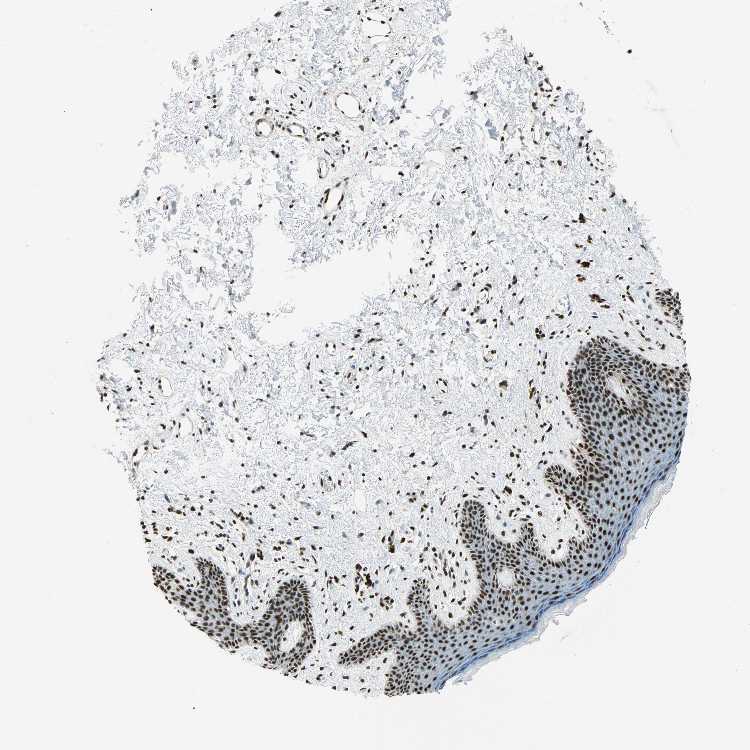

SKIN 1 - Antibody stainingi

Antibody staining in the annotated cell types in the current human tissue is reported as not detected, low, medium, or high, based on conventional immunohistochemistry profiling in selected tissues. This score is based on the combination of the staining intensity and fraction of stained cells.

Each image is clickable and will lead to virtual microscopy that enables deeper exploration of all samples and also displays staining intensity scores, fraction scores and subcellular localization as well as patient and tissue information for each sample.

Antibody HPA006385Antibody CAB004611

Langerhans HighHigh

Fibroblasts HighHigh

Keratinocytes HighHigh

Melanocytes HighHigh

SKIN 2 - Antibody stainingi

Epidermal cells HighHigh